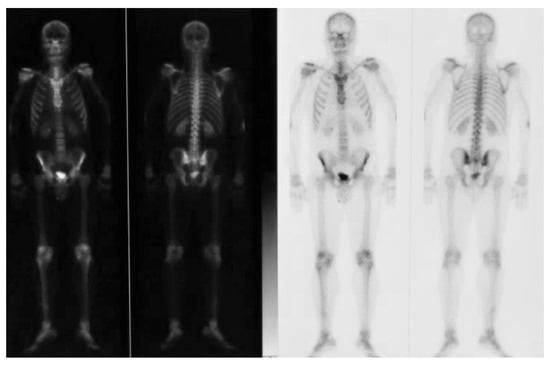

- Condylectomy

2.2. Second Step